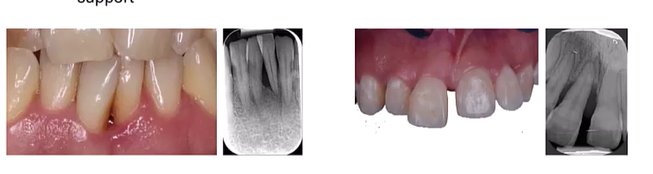

Assessment of risk profile: site level what are 3 main factors that can determine the local risk?

BOP No bleeding is a good indicator of stability rather than saying because there is bleeding there is instability

PPD and CAL

Suppuration

At tooth level, the main determinants of risk include? (5)

Crowding - plaque retentive factor

Furcation - applies only to multirooted teeth

Iatrogenic factors - overhanging fillings/prothesis

residual periodontal support

mobility (hypermobility and flaring)